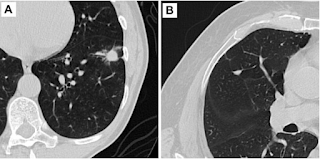

CT screening for early lung cancer leads to long-term survival

CANCER DIGEST – Nov. 27, 2022 – A new study shows that early detection of lung cancer with CT scanning dramatically increases long-term...